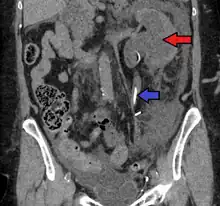

CT scan of bilateral hydronephrosis due to a bladder cancer

Massive hydronephrosis as marked by the arrow.- Renal ultrasonography of hydronephrosis[14]

- Stone causing hydronephrosis[14]